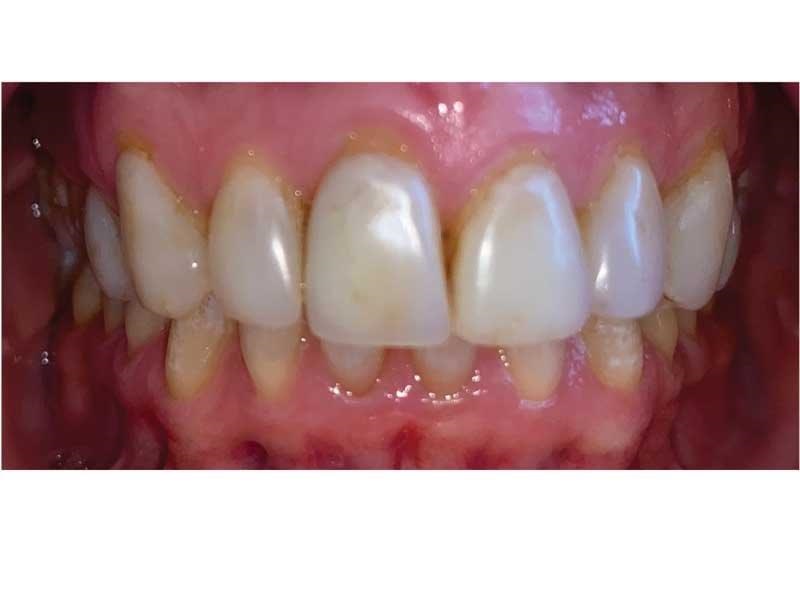

Meet Lorraine, who came into my office to “redo her bonding.” Lorraine had some upper anterior teeth done years ago with resin, which now was dull, stained and breaking down (Figs. 1–3). She had an amount of money in mind that she thought it would cost. She was very wrong.

Fig. 1

Fig. 2

Fig. 3